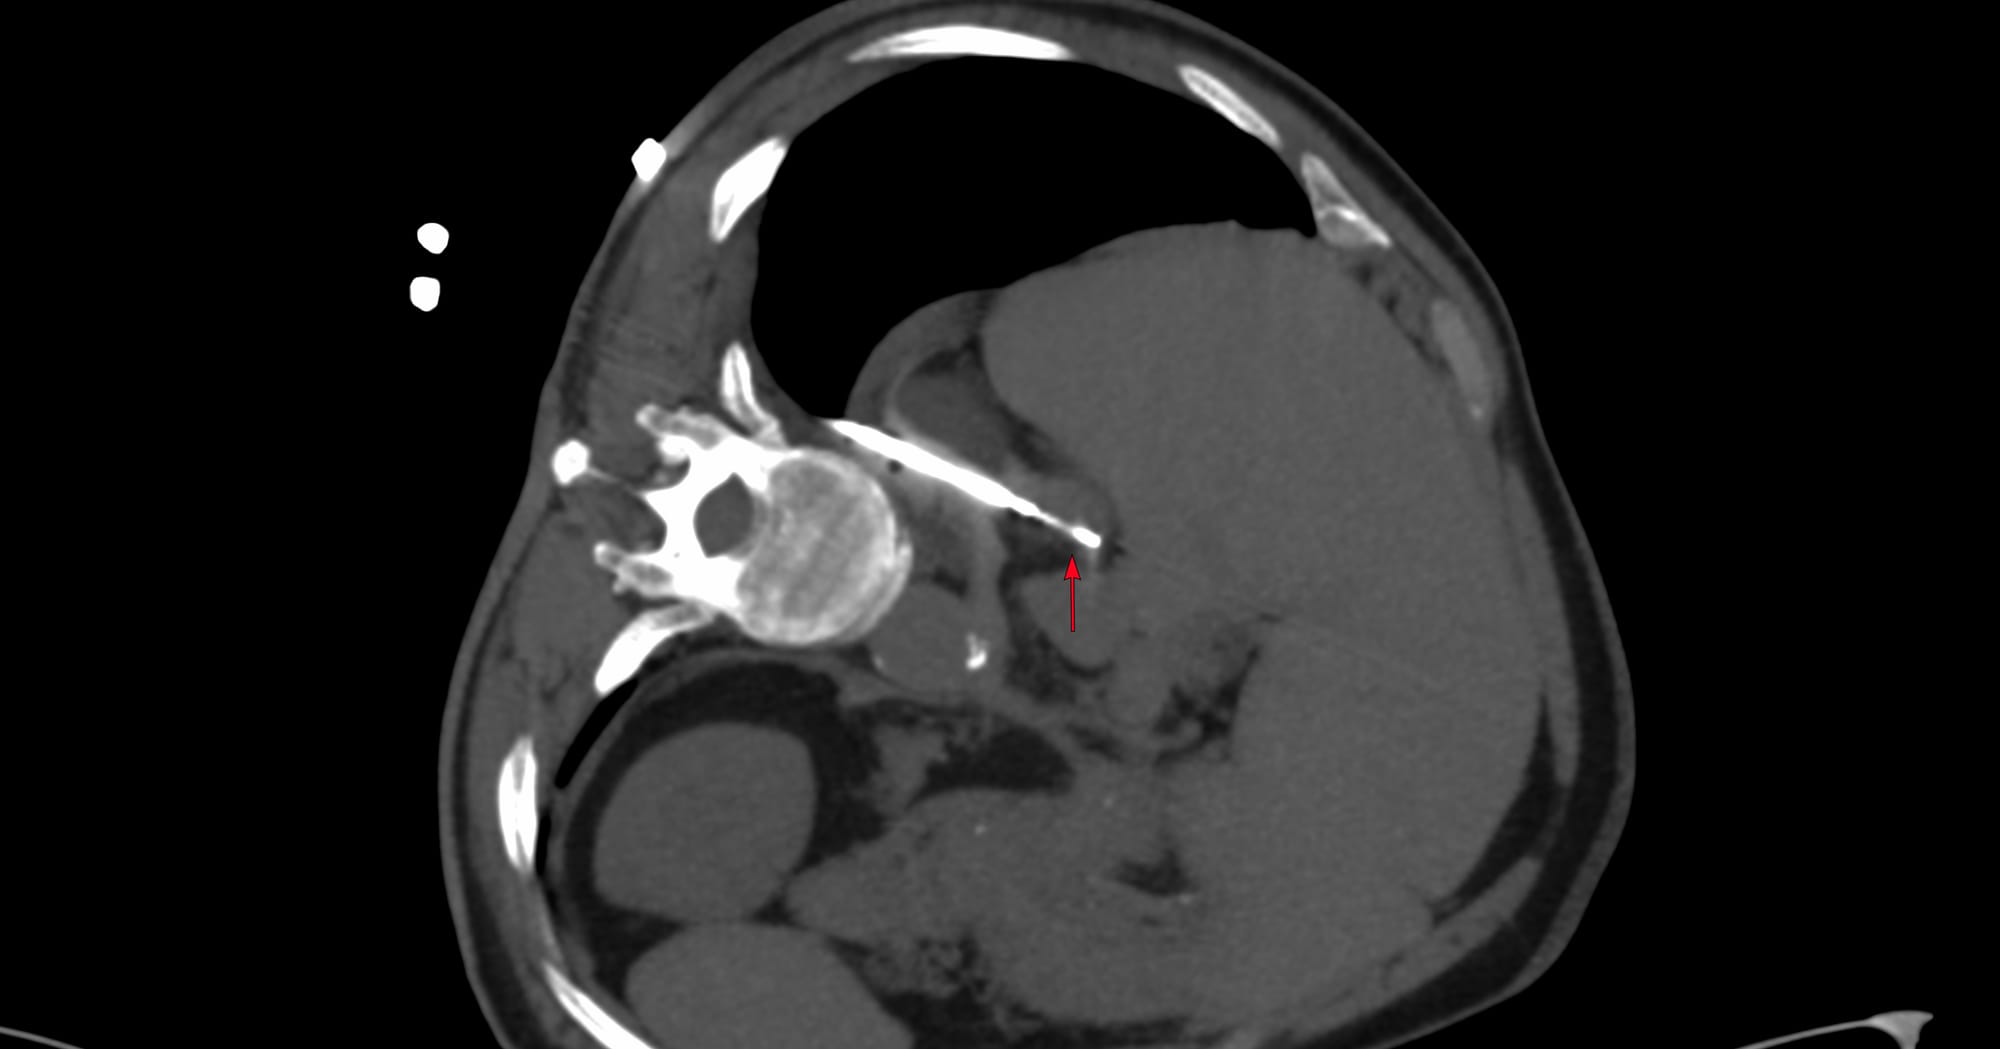

I will be discussing these 7 biopsy cases from Dec 2025, across different levels of difficulty.

YouTube Live Session - CT Guided Biopsy Cases from December 2025

7 cases of different levels of difficulty discussed live on 08 Jan 2026